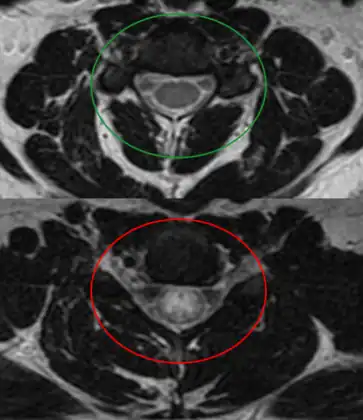

MRI of individual diagnosed with transverse myelitis -

Axial T2 MRI of cervical spine demonstrating normal cord signal (green circle) and increased T2 signal in the central cord (red circle).